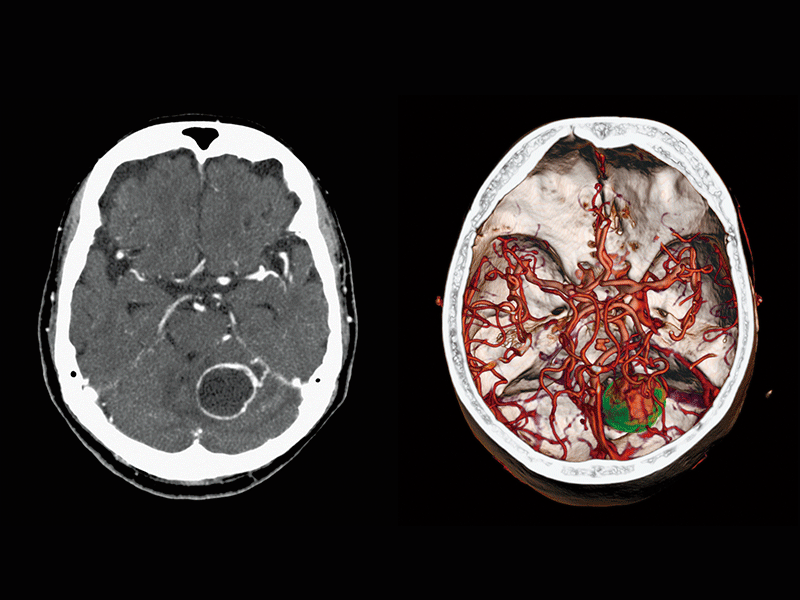

FBP(Left)

Intelli IPV(Right)

Brain tumor

Common carotid artery stenosis